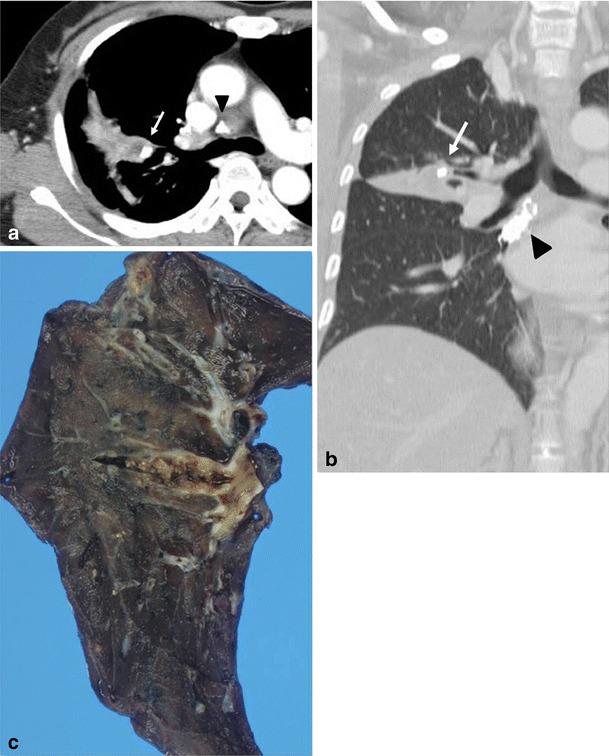

Thoracic actinomycosis can be radiologically divided into the parenchymal type, the airway type including bronchiectasis, the endobronchial form, and the mediastinum or chest wall involvement type.

• Important risk factors for thoracic actinomycosis are underlying respiratory disorders such as emphysema and chronic bronchitis. • Different CT patterns can be distinguished in thoracic actinomycosis: parenchymal, bronchiectatic, endobronchial and extrapulmonary. • Typical CT findings in the parenchymal pattern are a central low density within the parenchymal consolidation and adjacent pleural thickening.

胸放线菌病可在放射学上分为实质型、气道型(包括支气管扩张)、支气管内型和纵隔或胸壁受累型。

• 胸放线菌病可区分不同的 CT 模式:实质型、支气管扩张型、支气管内型和肺外型。

• 实质型的典型 CT 表现为实质浸润内的中央低密度影和相邻胸膜增厚。